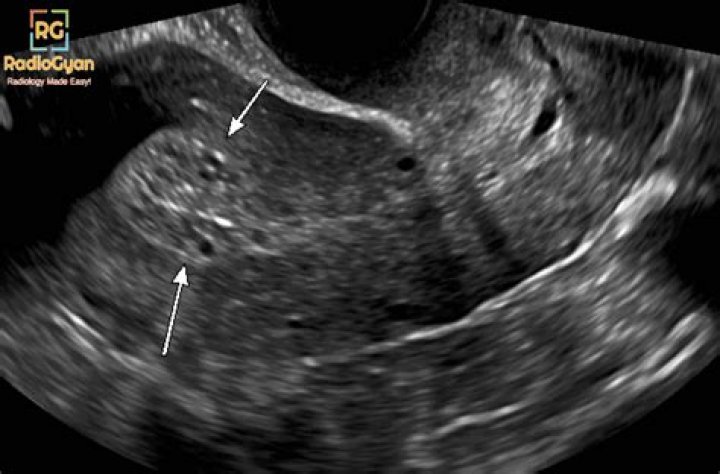

Endometrial hyperplasia is a condition of the female reproductive system. The lining of the uterus (endometrium) becomes unusually thick because of having too many cells (hyperplasia). It's not cancer, but in certain women, it raises the risk of developing endometrial cancer, a type of uterine cancer.

Among postmenopausal women with vaginal bleeding, an endometrial thickness ≤ 5 mm is generally considered normal, while thicknesses > 5 mm are considered abnormal4, 5.

What is the normal size of endometrial thickness?

suggested upper limit of normal is <5 mm. the risk of carcinoma is ~7% if the endometrium is >5 mm and 0.07% if the endometrium is <5 mm. on hormonal replacement therapy: upper limit is 5 mm.

What percentage of endometrial biopsies are cancerous?

Conclusions: In a postmenopausal woman without vaginal bleeding, if the endometrium measures > 11 mm a biopsy should be considered as the risk of cancer is 6.7%, whereas if the endometrium measures < or = 11 mm a biopsy is not needed as the risk of cancer is extremely low.